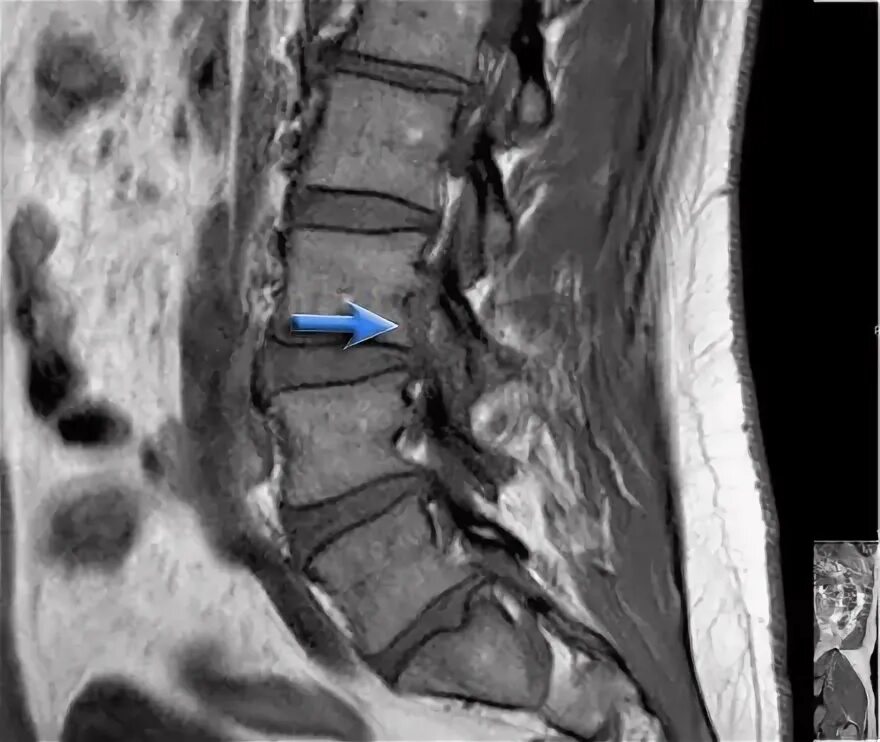

Протрузии l3 4 l4 5